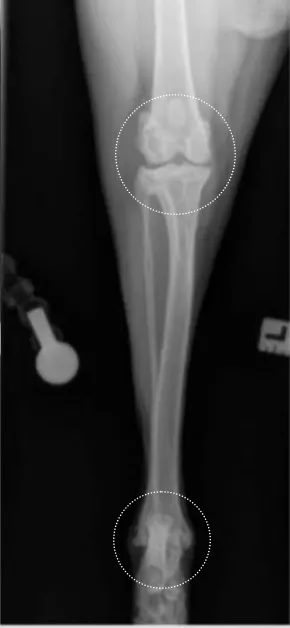

Author Insight

On the radiograph, the medial (A) and lateral (C) fabellae should be bisected by the medial and lateral femoral cortices (lines). The patella (B) should be centered in the patellar groove. The medial edge of the calcaneus (arrow) should bisect the distal intermediate ridge of the tibia (center of the curved line), ensuring a straight tarsus and distal tibia. If the stifle and tarsus (circles) are straight, the tibia and fibula will be straight. In the rare case of an angular or torsional deformity, achieving a straight view of the stifle and tarsus in 1 view may be challenging; straight views of the stifle and tarsus should thus be acquired individually.